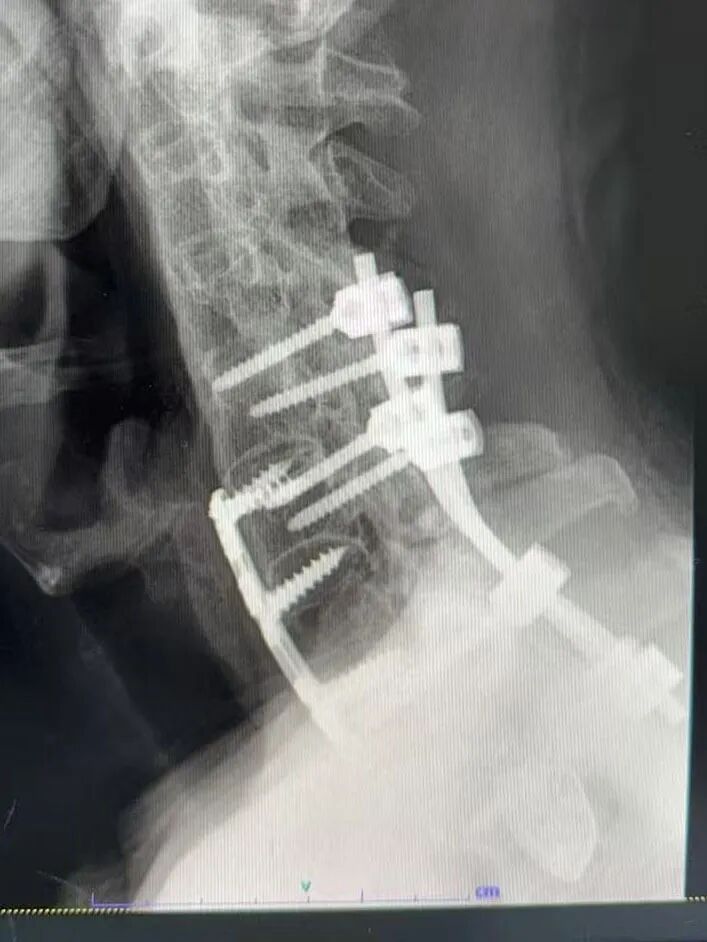

(手术前后X片检查对比)

整场手术历时约3小时,手术团队全神贯注,按照既定的手术方案,顺利完成了骨折复位、内固定植入等关键操作。手术过程中,每一个步骤都严谨有序,每一个细节都处理得恰到好处。经过3个小时的努力,手术终于成功完成,未发生任何并发症。

手术前后的X片对比显示,骨折端复位良好,内固定位置精准。这一结果让所有参与手术的医护人员都松了一口气,也为王先生的后续康复打下了坚实基础。手术的成功,不仅是手术团队精湛医术的体现,更是多学科协作的胜利。